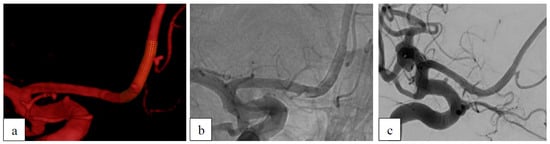

3.5.2. Ruptured Aneurysms

| 26 | f | V4 | left | dissecting | no | no | ASA+ Clopidogrel | D1 | 8 | D1 |

| 28 | f | P2/P3 | right | dissecting | yes | no | ASA+ Clopidogrel | A2 | 5 | D1 |

| 48 | m | V4 | left | dissecting | yes | no | ASA+ Clopidogrel | A3 | 6 | D1 |

| 60 | f | V4 | left | dissecting | yes | no | ASA | A3 | - | - |

| 4 | 48 | m | V4 | left | dissecting | yes | no | ASA+ Clopidogrel | A3 | 6 | D1 |